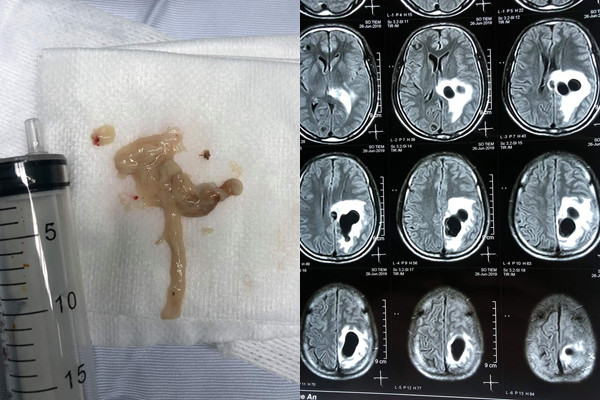

| Ổ sán lớn trong não bệnh nhân được lấy ra (ảnh trái) và hình ảnh ổ sán trên phim chụp CT não. Ảnh minh họa: Internet |

Kết quả chụp CT não cho thấy có 5 ổ sán nằm rải rác trong não, trong đó có một ổ sán lớn trên đỉnh đầu của bệnh nhân gây phù não. Bệnh nhân được chỉ định phẫu thuật để lấy được trọn vẹn ổ nang sán lớn khỏi não.